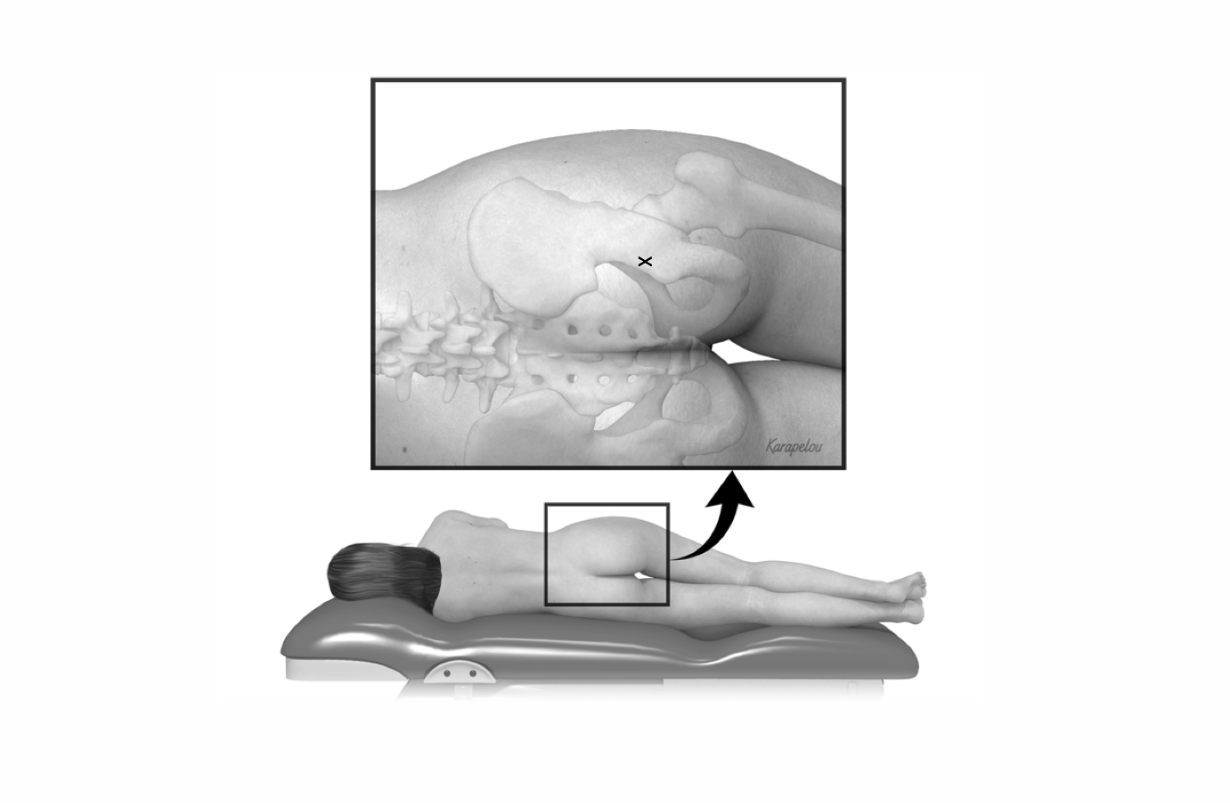

Piriformis Syndrome

DEFINITION: Entrapment of the sciatic nerve by the piriformis muscle in the buttock. BENEFICIAL POSES: Matsyendrasana, Parivrtta Trikonasana, Parivrtta Parsvakonasana. EXPLANATION: These poses stretch the piriformis muscle at various angles, which both increases its length, thereby reducing the compression on the sciatic nerve that passes just beneath it, but also reducing spasm (involuntary tightening) in the muscle. Done mindfully, these poses also increase a person's ability to control the muscle. The first REFERENCE: Fishman LM, Wilkins AN, Rosner B.Electrophysiologically identified piriformis syndrome is successfully treated with incobotulinum toxin a and physical therapy. Muscle Nerve. 2017 Aug;56(2):258-263. doi: 10.1002/mus.25504. Epub 2017 Apr 2. For fuller description of the syndrome and its treatment, see "Healing Yoga," L.M. Fishman, W.W.Norton.

SI Derangement, Sacroiliac Joint Derangement

DEFINITION: Misalignment of the joints between the sacrum and the right and left iliac bones. To test for it, stand behind the subject, placing your thumbs on the posterior superior iliac spines (PSIS). As the person moves forward, one thumb will often move up further than the other. Usually the painful side is the one that does not move, but this is not always the case. Generally derangement occurs as a movement of the sacrum along a diagonal axis, from the upper right corner of the sacrum to the lower left, in which case the upper left moves forward (or back) and the lower right moves back (or forward) . The axis around which the sacrum revolves may just as well be from the upper left to the lower right, in which case the upper right will move forward (or back) and the lower left will move back (or forward). BENEFICIAL POSES: Gomukhasana, Garudasana, Modified Mayurasana (quite modified, see video). EXPLANATION: Gomukhasana and Garudasana widen the SI joint by adducting the thighs and pulling the iliac bones apart. The modified Mayurasana raises the sacrum but not the iliac bones, enabling the sacrum to slide into its proper place on the right and left. REFERENCE:Fishman, L. "Healing Yoga." W.W. Norton. New York;2015: pp 47-53.